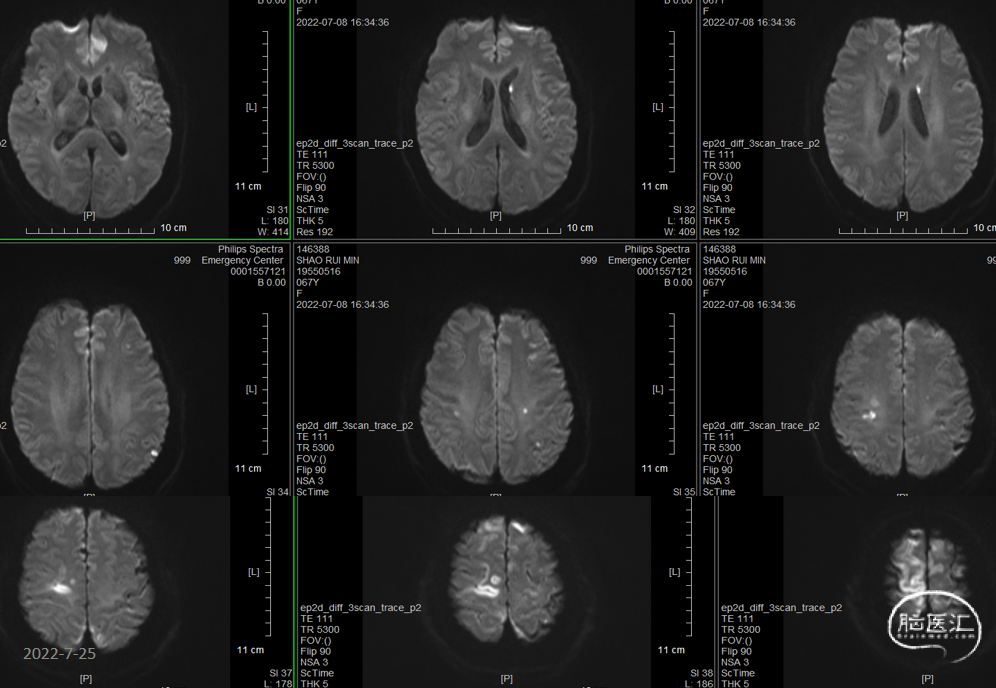

术后第三天查核磁:动脉瘤术后改变,蛛网膜下腔、脑室积血。双侧颞顶叶散多发脑梗塞。考虑左侧肢体活动不利为右侧脑梗塞所致。

术后第三天头颅MRA示:血管通畅。

2022-7-8术后第三天,语言正常,MRI右侧脑梗塞,考虑血管痉挛所致。腰穿!

●同时该患者左侧肢体有偏瘫表现,考虑为动脉瘤破裂后蛛网膜下腔出血刺激血管痉挛所致,给予尼莫地平缓解血管痉挛并疏通血管后,症状逐步好转。